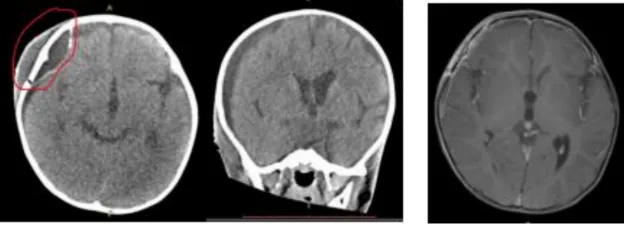

手术并没有引起进一步的神经功能障碍,但却出现了一些并发症。即硬膜下积液、尿崩症,用去氨加压素(Minerin)控制,后来又出现了耗盐综合征,继发低钠血症和癫痫,用静脉高渗溶液、口服钠片和左乙拉西坦(Keppra)治疗。

术后阶段,该患儿还出现了脑脊液渗并自行痊愈。事实上,术后核磁共振成像(2021年8月18日)也显示术后硬膜下血肿已得到解决,该血肿在之前的术后CT扫(2021年7月26日)中存在。

确实,术后核磁共振成像(2021年8月18日)也显示在之前的术后CT扫描(2021年7月26日)中存在的术后硬膜下积液的问题已得到解决。